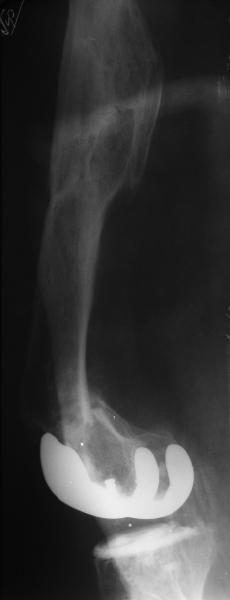

Глубокоуважаемые коллеги, Мужчина 41 года поступил с повторным (предыдущий в 2001 г.) переломом (3-недельной давности) над протезом коленного сустава.

В 1994 множественная травма, в том числе открытый перелом надколенника, осложнившийся гнойным артритом, и на этой же стороне перелом диафиза бедра (лечили в аппарате). В 1998 г. выполнено эндопротезирование коленного сустава.Предыдущий перелом (3 года назад) лечили консервативно, сросся при неустраненном смещении дистального блока бедра кзади ~ на 1 см.Амплитуда движений в коленном суставе перед последним переломом была ~90 градусов. Ходил без дополнительной опоры.Снимки в приложении. Какие будут предложения по поводу оперативного лечения в нынешней ситуации? У нас споры между ретро- и антеградным закрытым интрамедуллярным остеосинтезом.

A male 41 years old transferred to our unit with 3 week old femoral fracture near the knee prosthesis after a mimimal fall. In 1994 he sustained multiple injury with open patella fracture (complicated with septic arthritis), and ipsilateral femoral shaft fracture treated by ex-fix. TKA performed in 1998. In 2001 he got a periprosthetic fracture which was treated nonoperatively and healed with ~1 cm dorsal displacement of the distal femoral block. Knee ROM prior the recent injury was about 90-95 degrees. He didn't use walking aid.Images attached. I request your suggestions regarding surgical options in the situation? We mostly discuss ante- vs retrograde closed nailing.

В итоге сделали антеградный остеосинтез. В дистракторе свежий перелом вправился сразу, а вот старый - оставил проблему, дистальный отлмомк остался все равно кзади. И гвоздь бы прошел кпереди от него, а ретроградный - перфорировал бы передний кортекс. Так что пришлось еще сделать чрескожную остеотомию через перелом, чтобы малость мобилизовать дистальный отломок. Снимки в прилжении.

The radiographs look excellent and a good outcome would be anticipated. The idea to osteotomize the femur shaft to compensate for the prior shaft malunion was clever and should work fine.

I can't actually see the osteotomy on either radiograph. Is it more proximal than we see in these radiographs or so well aligned as to be not visible?